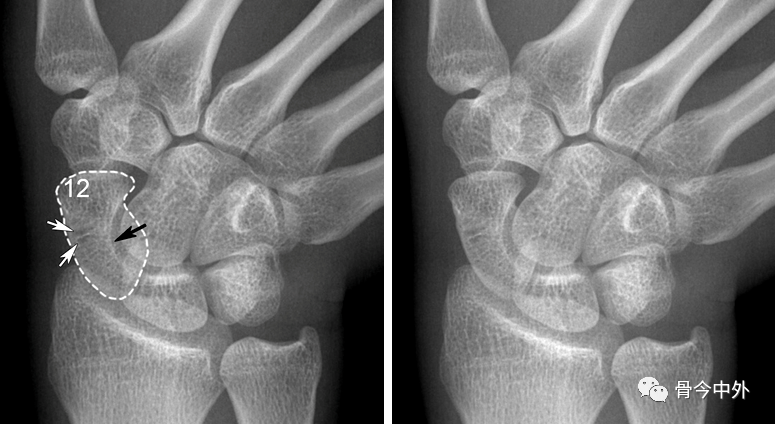

图3 成人期腕关节正侧位及舟骨蝶位片。12.舟骨结节。黑色箭头:舟骨腰部;白色箭头:舟骨滋养血管影。